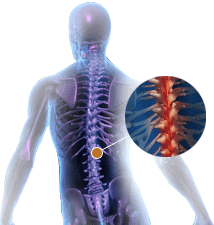

Spine Injuries

Spinal injuries are the most common injuries that may occur while playing, performing normal activities